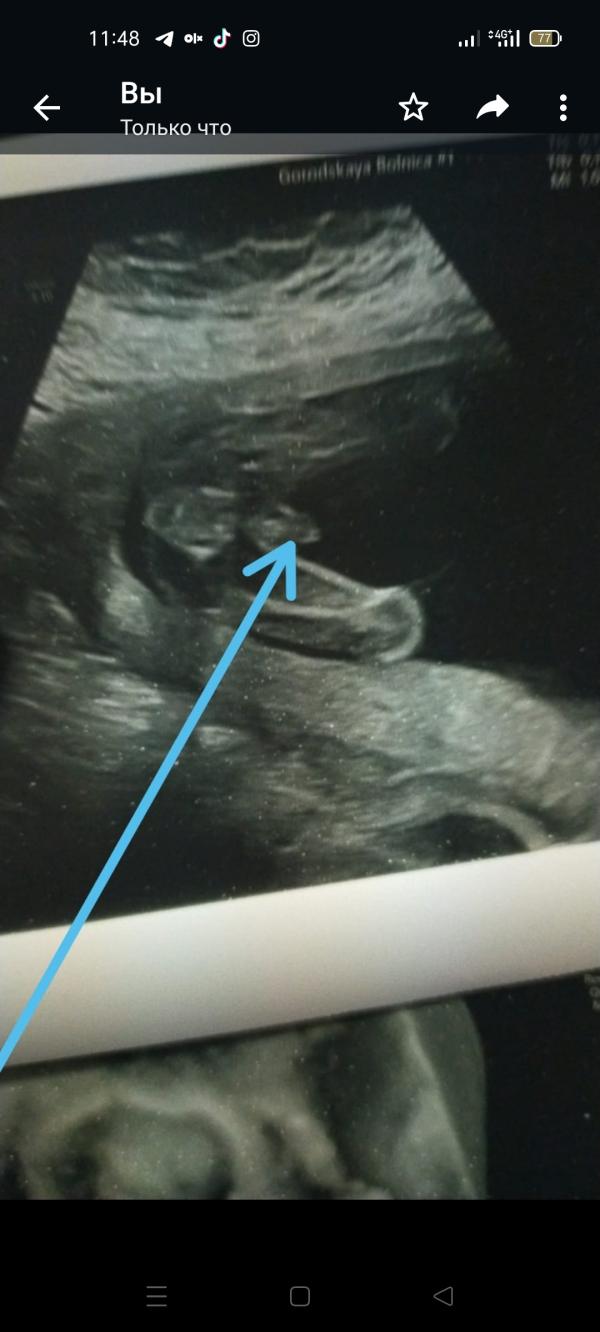

Хвала Аллаху! Мужик 100 — все в порядке, делимся результатами и впечатлениями

Хвала Аллаху все норм. Мужик 100%